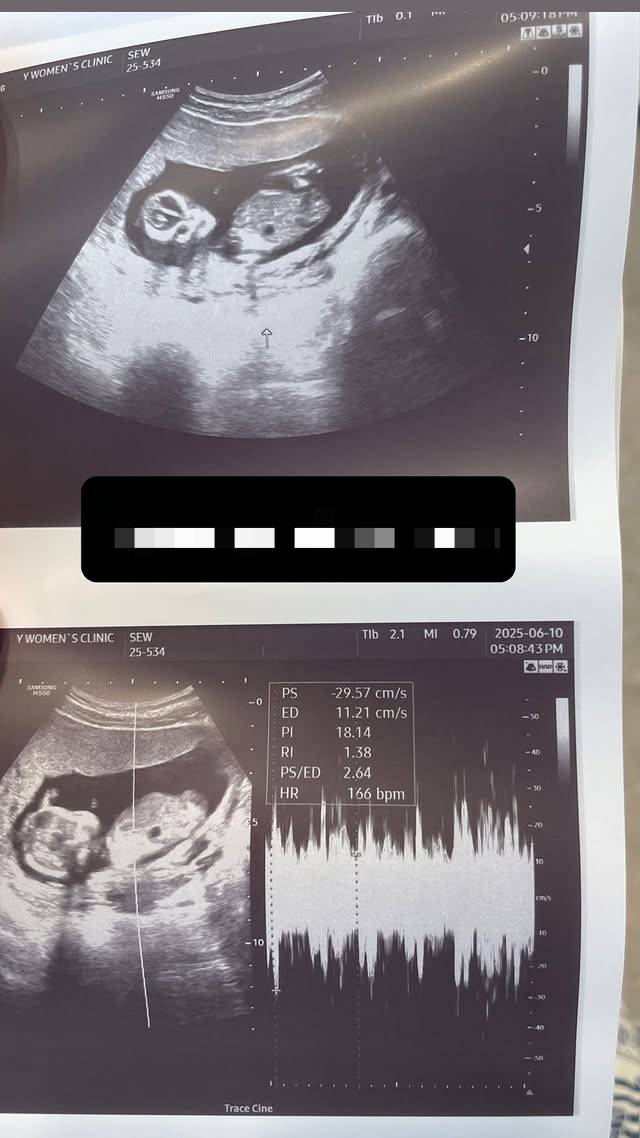

서민재는 현재 A씨와의 사이에서 임신한 아기를 뱃속에 품고 있다. 정확한 임신 시기와 출산 예정일은 공개된 바 없지만, 서민재는 지난달 임신 소식을 의미심장하게 공개해 화제를 모았다.

이외에도 서민재는 아기 초음파 사진과 함께 "짐승도 자기 새끼는 안 버려"라는 말을 전하며 A씨의 행동에 분노했다.